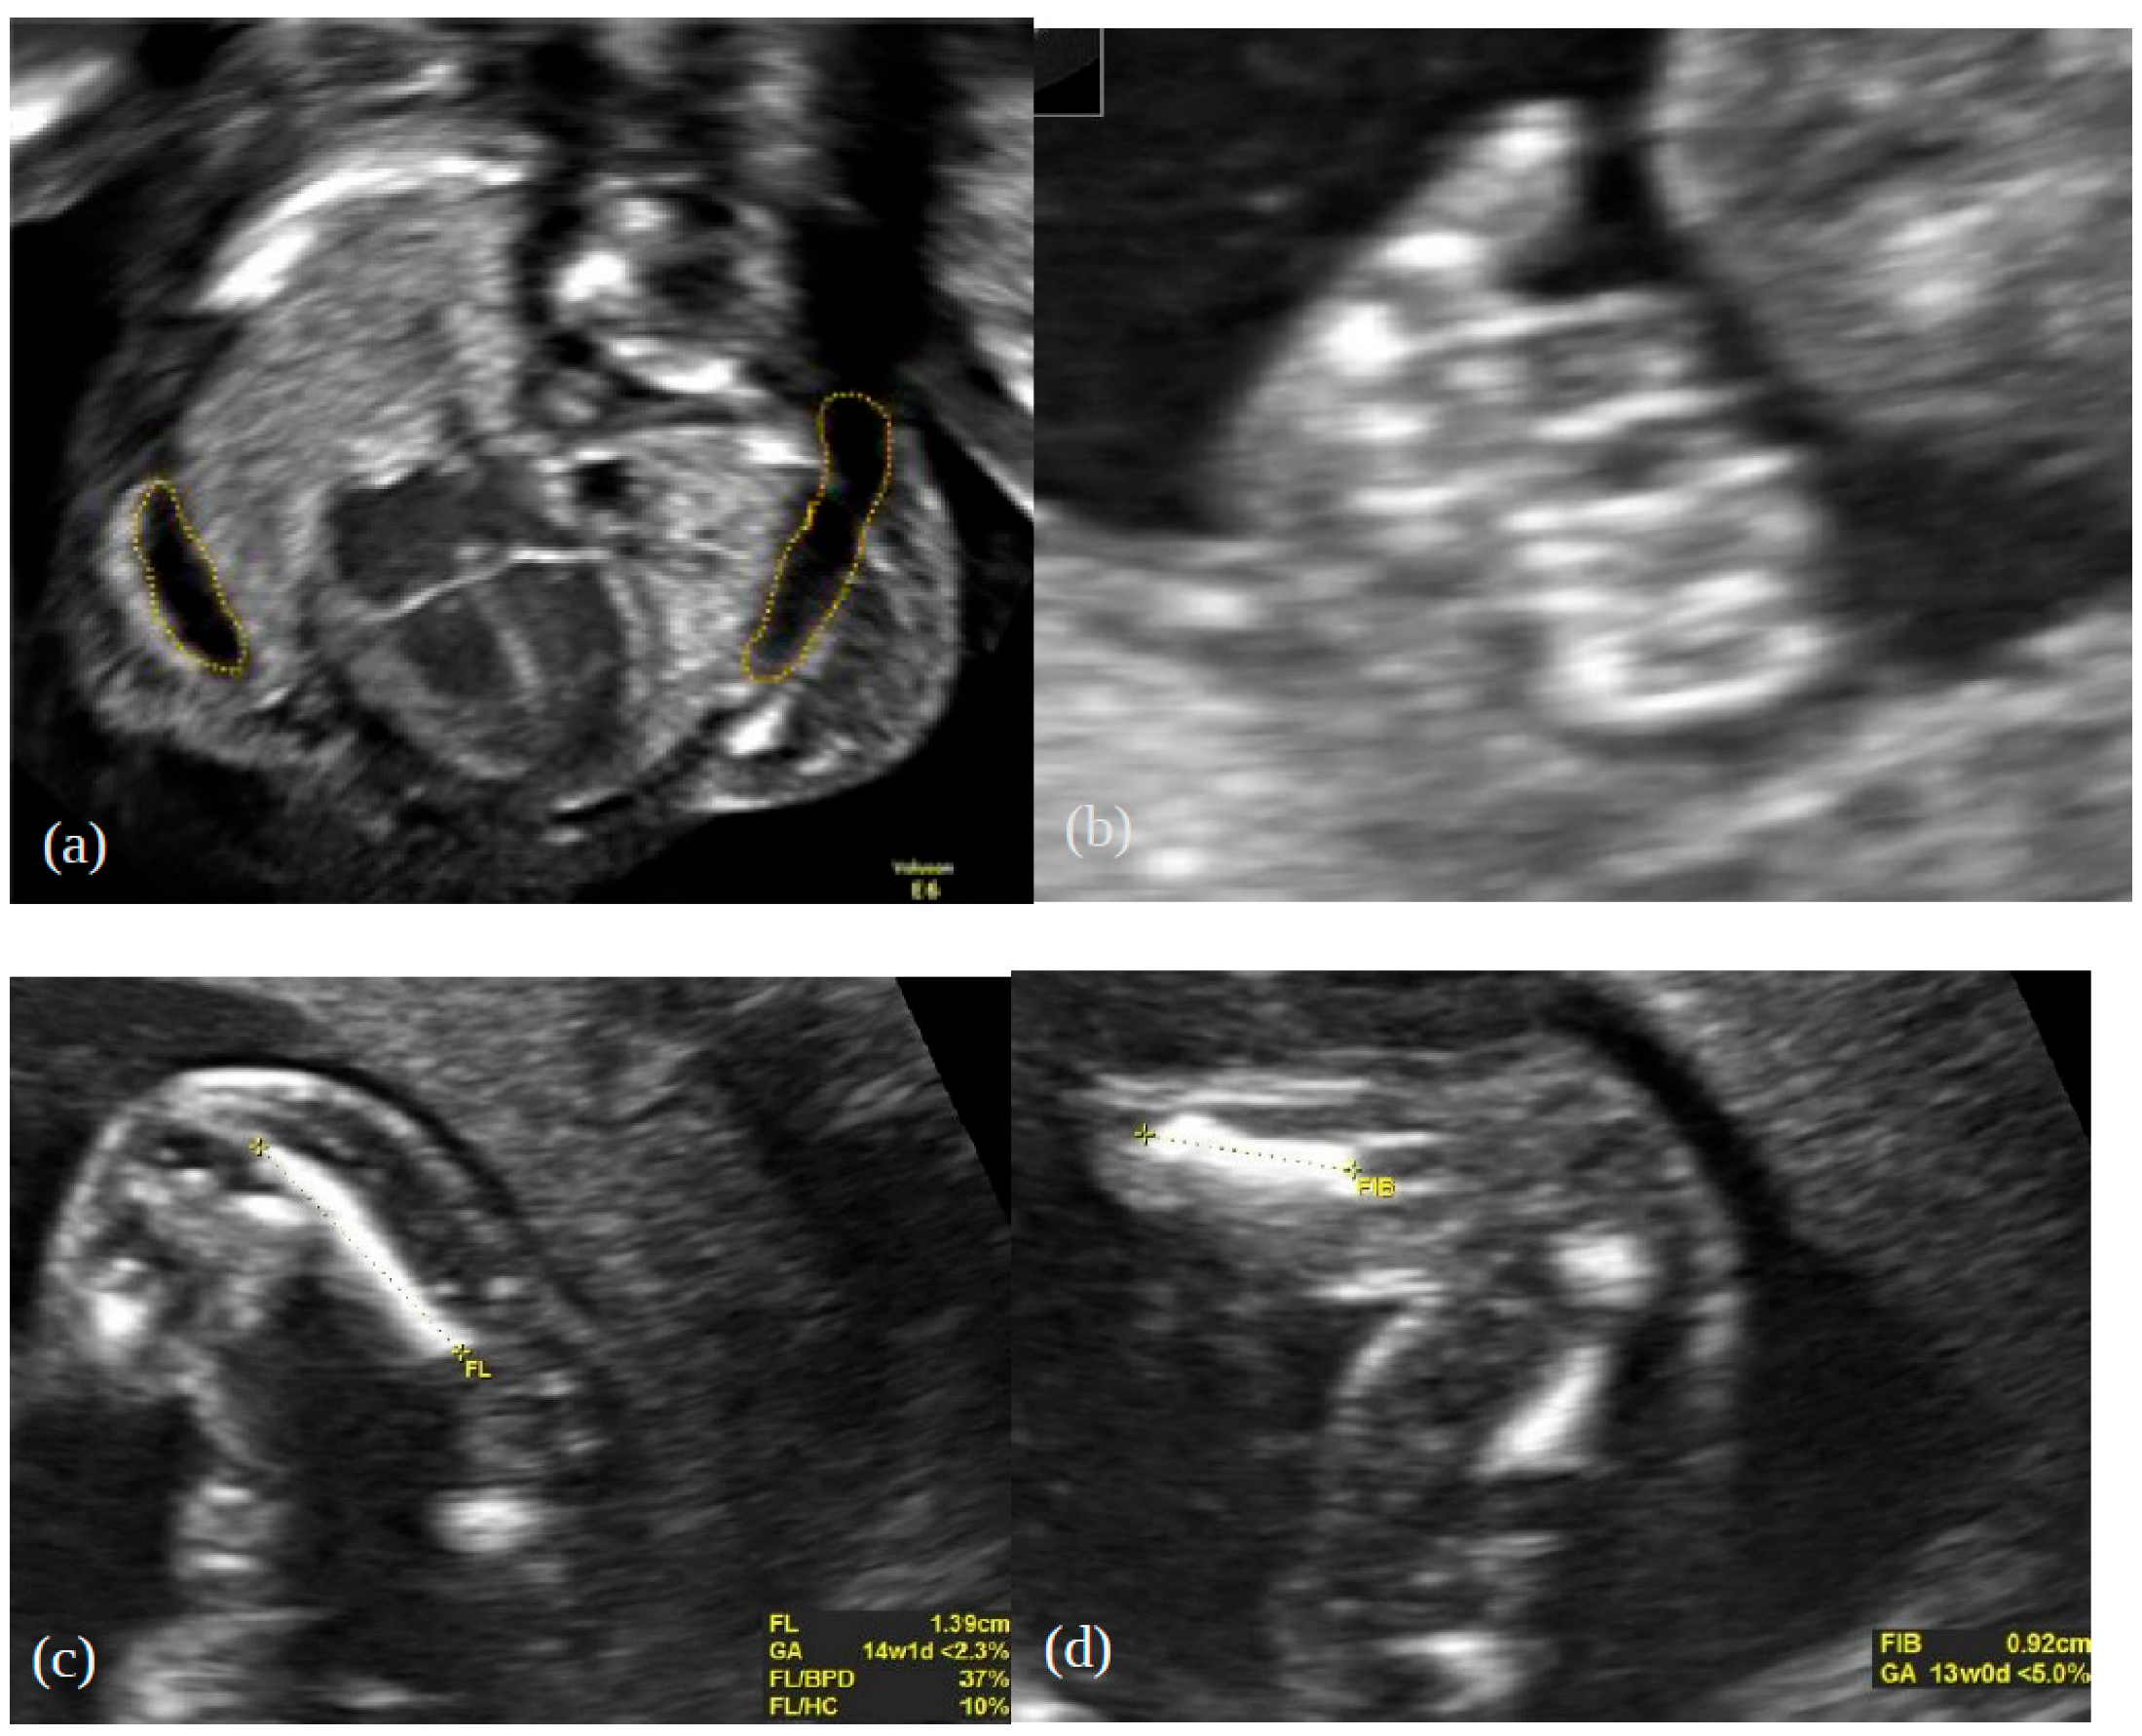

2. Case Report